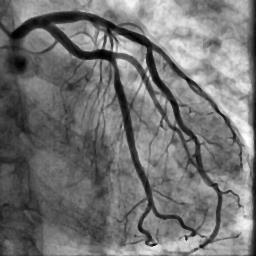

Blood vessel segmentation is crucial for many diagnostic and research applications. In recent years, CNN-based models have leaded to breakthroughs in the task of segmentation, however, such methods usually lose high-frequency information like object boundaries and subtle structures, which are vital to vessel segmentation. To tackle this issue, we propose Boundary Enhancement and Feature Denoising (BEFD) module to facilitate the network ability of extracting boundary information in semantic segmentation, which can be integrated into arbitrary encoder-decoder architecture in an end-to-end way. By introducing Sobel edge detector, the network is able to acquire additional edge prior, thus enhancing boundary in an unsupervised manner for medical image segmentation. In addition, we also utilize a denoising block to reduce the noise hidden in the low-level features. Experimental results on retinal vessel dataset and angiocarpy dataset demonstrate the superior performance of the new BEFD module.

翻译:近些年来,有线电视新闻网的模型导致分离任务突破,然而,这类方法通常会失去物体边界和对船只分割至关重要的微妙结构等高频信息;为解决这一问题,我们提议加强边界和地貌分解模块,以促进网络能力,在语义分解中提取边界信息,这种信息可以以端到端的方式纳入任意编码器-分解器结构。通过引入索贝尔边缘探测器,网络能够在之前获得更多边缘,从而以不受监督的方式加强医疗图像分解的边界。此外,我们还利用一个分解区块来减少低层特征中隐藏的噪音。关于再生容器数据集的实验结果和血管合成数据集显示了新的BEFD模块的优异性性表现。